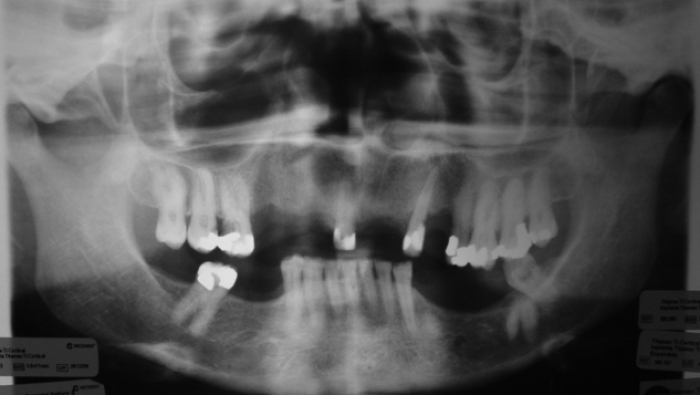

Rx Final